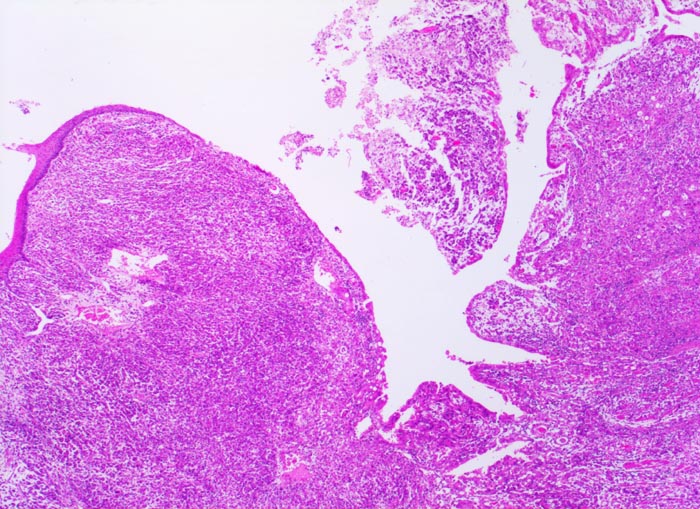

Makroskopisch können nach Borrmann (> 5050) polypoide Tumoren, ulzerierte Tumoren mit Randwall, ulzerierte Tumoren mit Invasion der Magenwand und diffus infiltrierende Tumoren (=Linitis plastica (> 3315)) unterschieden werden.

Die ersten beiden Typen entsprechen histologisch meist einem intestinalen Typ nach Lauren (> 1342). Diese Tumoren sind scharf begrenzt, bilden tubuläre oder papilläre Strukturen wie die Dickdarmkarzinome, sind meist assoziiert mit bekannten umweltbedingten Risikofaktoren und haben eine bessere Prognose.

Beim diffusen Typ nach Lauren infiltrieren Einzelzellen oder Zellstränge, meist mit Siegelringzellanteilen diffus die Magenwand. Eine Drüsenbildung ist nicht erkennbar. Dieser Tumortyp tritt bei relativ jungen Patienten auf und ist mit genetischen Faktoren assoziiert (positive Familienanamnese). Wegen des diffus infiltrativen Wachstums ohne makroskopisch sicher erkennbare Grenze müssen diese Tumoren mit einem grösseren Sicherheitsabstand operiert werden. Siegelringkarzinome machen rund 20% aller Magenkarzinome aus.